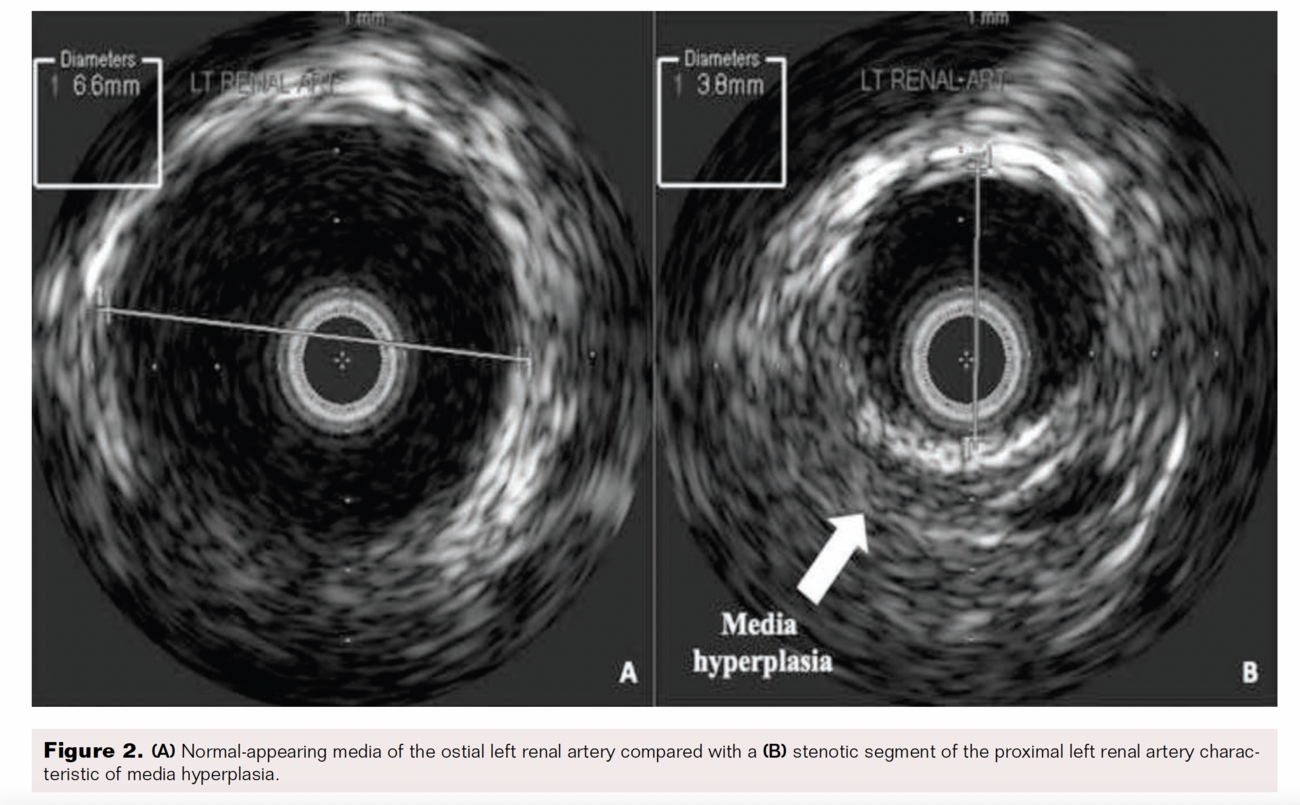

A 22-year-old man presented to the clinic with a new onset of elevated blood pressure ranging 130-150/80-90 mmHg. He denied a family history of hypertension, recent over-the-counter decongestant use, tobacco or illicit drug use, excessive alcohol intake, or a history of sleep apnea. His first elevated blood pressure was incidentally found 2 months earlier when he tested positive for SARS-CoV-2 and once more while donating blood plasma. The patient otherwise had no symptoms. He was started on amlodipine 10 mg once daily and telmisartan 80 mg once daily. At the 1-month follow-up, he continued to have unresolved hypertension, so chlorthalidone 25 mg once daily was added. His lab work showed renin activity elevated at 20 ng/mL/h with normal aldosterone. His metanephrine and thyroid-stimulating hormone/thyroxine levels were normal. His basic metabolic panel (BMP) showed elevated creatinine at 1.4 mg/dL and decreased sodium at 133 mmol/L but was otherwise unremarkable. A renal ultrasound Doppler revealed a normal proximal left main renal artery peak velocity at 105 cm/s; however, the mid-left main renal artery peak velocity was elevated at 312 cm/s, suggesting RAS. A computed tomography (CT) angiogram of the abdomen and pelvis showed smooth tapered narrowing at the proximal left renal artery, with peak narrowing measuring 2 to 2.5 mm in diameter approximately 8 mm distal to the ostium and at least moderate distal post-stenotic dilation. The remainder of the arteries, including an accessory artery to the right kidney, appeared to be normal bilaterally. The patient subsequently underwent angiography, which found discrete 80% stenosis in the left proximal renal artery and severe post-stenotic aneurysmal dilation (Figure 1). The right renal artery angiography was normal. Intravascular ultrasound showed no atherosclerotic plaque, web plexus, or calcification in the left renal artery (Figure 2). Balloon angioplasty of the left renal artery was performed using a 0.014" Hi-Torque All-Star guidewire (Abbott) and a 6 mm Viatrac balloon (Abbott) at 7 atm max pressure. An I.V. ultrasound was done using an Eagle Eye Platinum catheter (Philips). Post-intervention residual stenosis was noted at 20%. The patient was placed on aspirin 81 mg daily and clopidogrel 75 mg daily for 3 months. On a subsequent follow-up, the patient showed significant blood pressure improvement, and his medications were gradually stopped. His blood pressure normalized to 115–120/80 mmHg, and repeat lab values showed an unremarkable BMP and urinalysis.